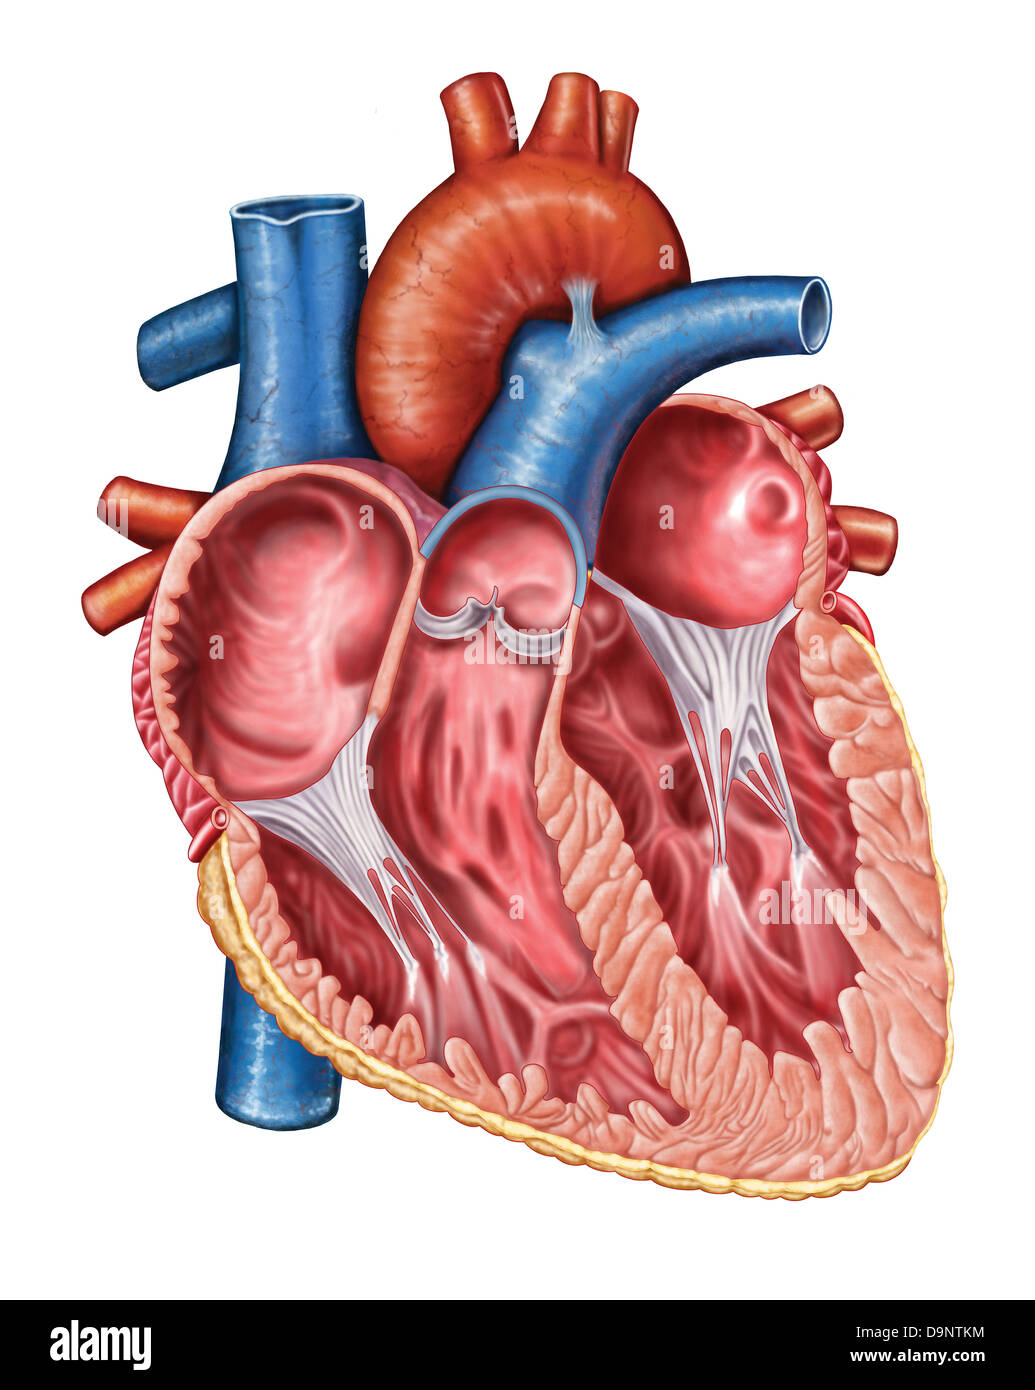

Internal view of the human heart. Stock Photohttps://www.alamy.com/image-license-details/?v=1https://www.alamy.com/stock-photo-internal-view-of-the-human-heart-73471736.html

Internal view of the human heart. Stock Photohttps://www.alamy.com/image-license-details/?v=1https://www.alamy.com/stock-photo-internal-view-of-the-human-heart-73471736.htmlRFE7EWXG–Internal view of the human heart.

Interior of human heart. Stock Photohttps://www.alamy.com/image-license-details/?v=1https://www.alamy.com/stock-photo-interior-of-human-heart-57643368.html

Interior of human heart. Stock Photohttps://www.alamy.com/image-license-details/?v=1https://www.alamy.com/stock-photo-interior-of-human-heart-57643368.htmlRFD9NTKM–Interior of human heart.